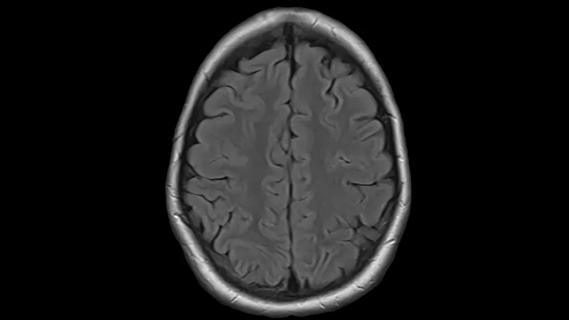

December 16, 2025/Neurosciences/Brain Tumor

Emerging Technologies in Brain Tumor Management (Podcast)

Advances in genomics, spinal fluid analysis, wearable-based patient monitoring and more